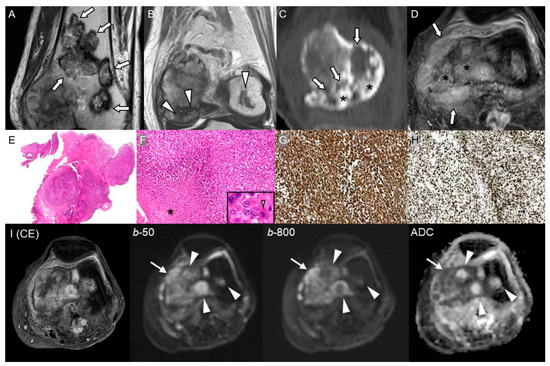

Malignant Transformation of Musculoskeletal Lesions with Imaging–Pathology Correlation—Part 1: Bone Lesions

by Hyang Sook Jeong, Seul Ki Lee, Jee-Young Kim, Changyoung Yoo and Min Wook Joo

Background/Objectives: Malignant transformation of bone lesions, although rare, poses a major diagnostic and clinical challenge. Common benign lesions (e.g., osteochondroma, enchondroma, fibrous dysplasia, giant cell tumor), non-tumorous conditions (e.g., chronic osteomyelitis, irradiated bone, infarction), and low-grade malignancies (e.g., low-grade osteosarcoma, chondrosarcoma) can evolve [...] Read more.

Background/Objectives: Malignant transformation of bone lesions, although rare, poses a major diagnostic and clinical challenge. Common benign lesions (e.g., osteochondroma, enchondroma, fibrous dysplasia, giant cell tumor), non-tumorous conditions (e.g., chronic osteomyelitis, irradiated bone, infarction), and low-grade malignancies (e.g., low-grade osteosarcoma, chondrosarcoma) can evolve into aggressive malignancies through distinct genetic, molecular, and microenvironmental pathways. Recognizing early malignant transformation on imaging is crucial for timely diagnosis and management. Methods: This review synthesizes current imaging characteristics, pathologic mechanisms, and clinical risk factors associated with malignant transformation of benign and low-grade malignancy bone lesions. Results: Atypical imaging findings and inaccurate biopsies can delay diagnosis. Aggressive features—such as cortical destruction, heterogeneous enhancement, and loss of internal matrix—should prompt further pathologic evaluation. Advanced imaging and a multidisciplinary approach with integrated clinicoradiologic–pathologic review are essential to minimize missed diagnoses. Patients with risk factors such as genetic syndromes, prior denosumab therapy, inadequate surgery, or prior radiation therapy require close monitoring or timely intervention. Conclusions: Radiologic–pathologic correlation remains central to distinguishing benign from malignant lesions. This review article emphasizes a comprehensive imaging-pathology overview of benign and low-grade malignancy bone lesions with malignant potential, aiming to improve diagnostic accuracy and outcomes in orthopedic oncology. Full article